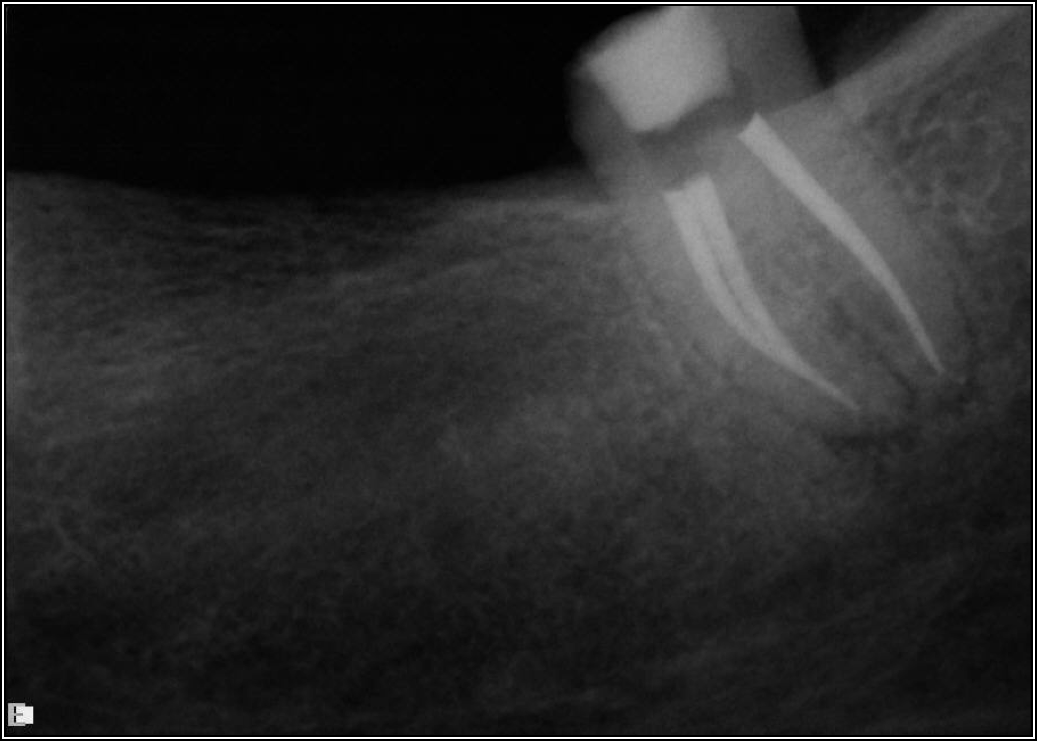

Ultimately, the aim in endodontics is to preserve the tooth as long as possible for the patient. A clinician may want to do a root canal but must face realistic concerns, such as not having enough tooth.Figure 1 shows a case where the clinician was able to access four canals through a zirconium crown, with limited access. Generally, it is preferable to err on the side of opening larger and cleaning out well. If the access is too small, three problems arise: (1) clinicians may not clean effectively; (2) there is a greater chance of separation because there is not enough of a straight path, and (3) canals may be missed. Conversely, if clinicians open too large, they can destroy the tooth. There is a happy medium where the result is fine-tuned and engineered perfectly. Although the perfect result is not always possible or ideal, clinicians continue to strive for it. The best approach is to find the canals and then open them up under a microscope to get enough access. This gives the clinician whatever shape is needed for conservative access.

Fig 1. Limited access.

Figure 1